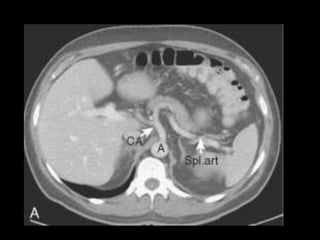

PÂNCREAS-VASOS

AORTA

TRONCO CELÍACO

MESENTÉRICA SUPERIOR

ESPLÊNICA

PANCREÁTICA DORSAL, MAGNA E TRANSVERSA

PANCREATICODUODENAIS SUP E INF

VEIA PORTA